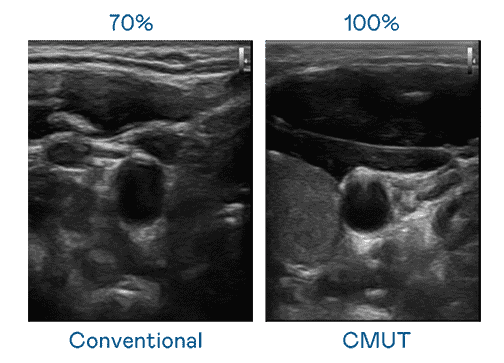

CMUT 技术是一种用电容式微机电元件来产生超音波讯号的技术。。与传统 PZT 压电式技术相比,,CMUT 频宽增加 30%,,更宽频的超音波讯号让影像解析度大幅提升,,,,是实现高影像品质医疗超音波扫描、、促进精准医疗发展的关键技术。。。。

超音波影像的解析度高低,,首先取决于探头能发出的讯号频宽。。。。蓝狮在线 CMUT 可提供高清晰的超音波讯号,,,,提供高频宽、、高灵敏度、、、影像纹理细节更高的超音波影像,,,,协助医护人员缩短影像判读时间及利用精准的医疗影像进行诊断。。